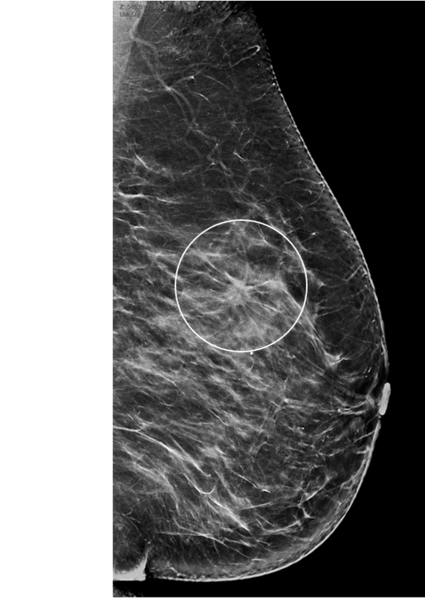

Systematische Brustkrebs-Früherkennung mit Digitaler Brust-Tomosynthese (DBT) und synthetischer 2D-Bildgebung (Foto: UKM-Radiologie Münster)

Die hohe Zahl der teilnehmenden Frauen belegt nach den Worten von Studienleiter Prof. Dr. Walter Heindel die hohe Akzeptanz der systematischen Brustkrebs-Früherkennung im deutschen Screening-Programm. Der Direktor der Klinik für Radiologie und Leiter des Referenzzentrums Mammographie am Universitätsklinikum Münster (UKM) berichtet von weltweit hohen Erwartungen an die Studie. Die Weiterentwicklung der digitalen Mammographie zur Brust-Tomosynthese biete eine Technologie, die, so der Radiologe, „durch die Berechnung dreidimensionaler Datensätze potentielle Gewebeüberlagerungen in der Brust reduziert und die daher diagnostische Vorteile ermöglichen kann“. Im ersten Schritt will die Forschungsgruppe den Kenntnisstand einer gesteigerten Brustkrebsdetektion im Screening beurteilen. Konkret bedeutet das: Was kann im Sinne der Frauen zusätzlich erreicht werden, was das 2D-Mammographie-Screening vorher nicht konnte? Als zweite Hypothese wird die Quote von Mammakarzinomen unter Frauen in einem Zeitraum von zwei Jahren nach Screening-Teilnahme zwischen der Tomosynthese-Testgruppe und der Kontrollgruppe verglichen.

Frauen, die sich für eine Teilnahme am Screening entschieden hatten, wurden für die Datenerhebung der Studie nach dem Zufallsprinzip und mit einer 50:50-Chance entweder der Gruppe mit Standard-Mammographie zugeordnet oder der Gruppe mit Tomosynthese und daraus errechneter synthetischer Mammographie. In beiden Gruppen werden die Entdeckungsraten von Brustkrebs und die Häufigkeiten der Abklärungsdiagnostik miteinander verglichen. Die Zuweisung erfolgt mittels einer Software und kann durch niemanden beeinflusst werden. Fachleute nennen das eine randomisierte klinische Studie. Frauen in Nordrhein-Westfalen und Niedersachsen erhielten seit 2018 zusammen mit ihrer regulären schriftlichen Einladung zum Screening nach dem Zufallsprinzip das Angebot, an der Studie teilzunehmen. Die ersten Zwischenergebnisse zu ToSyMa werden Ende 2021 erwartet.